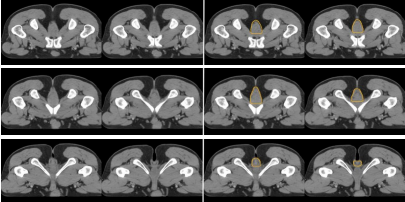

i) 高危復發區合集圖(CT 層厚 0.5 cm,俯臥位)(圖 14)。下表 示出高危復發區顏色。

表 直腸癌高危復發區顏色

圖 14 直腸癌高危復發區合集圖